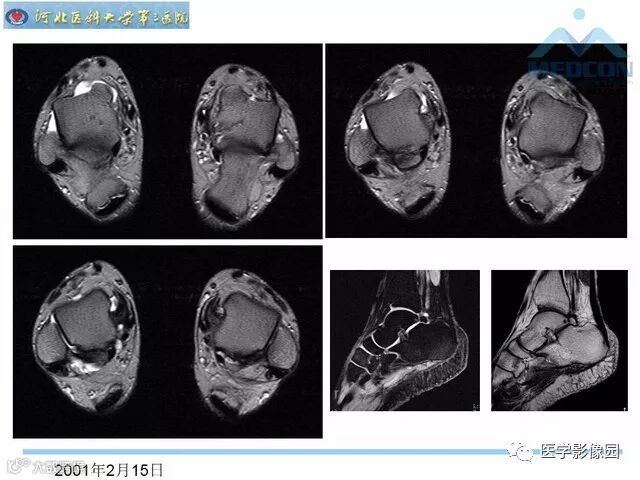

踝关节撞击综合征影像诊断,干货满满,值得收藏!

导读:踝关节撞击综合征影像诊断。干货满满,值得收藏!

踝关节撞击综合征影像诊断。干货满满,值得收藏!